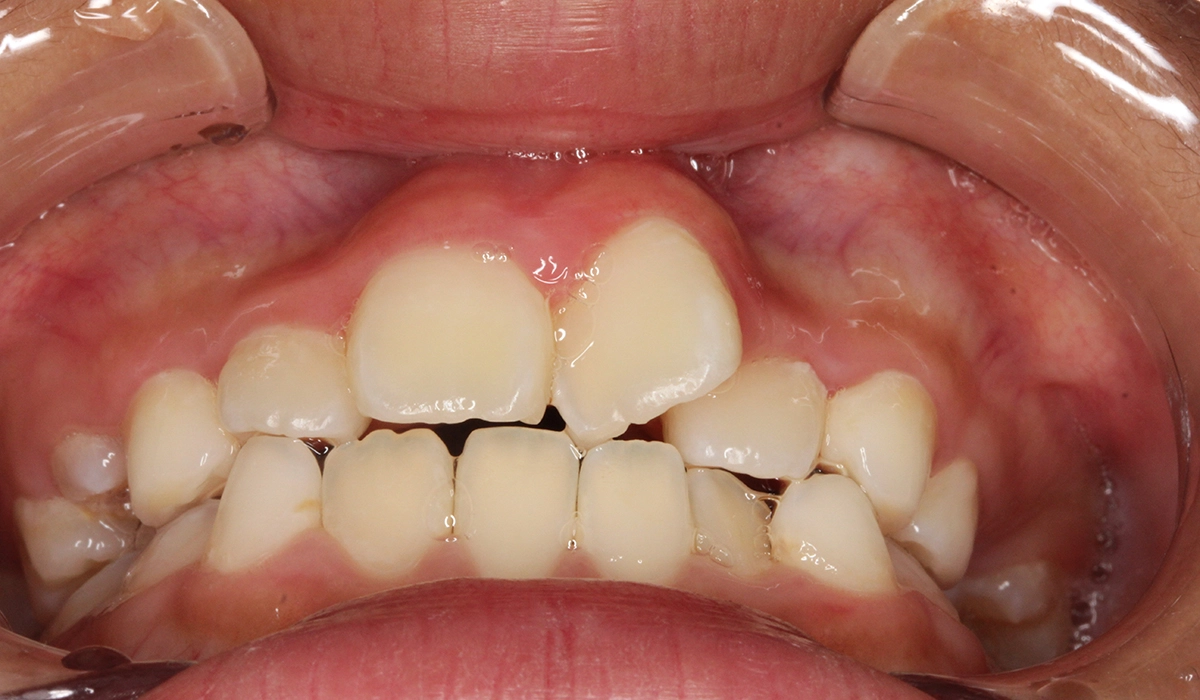

術前:前歯部あおり

術後:前歯部あおり